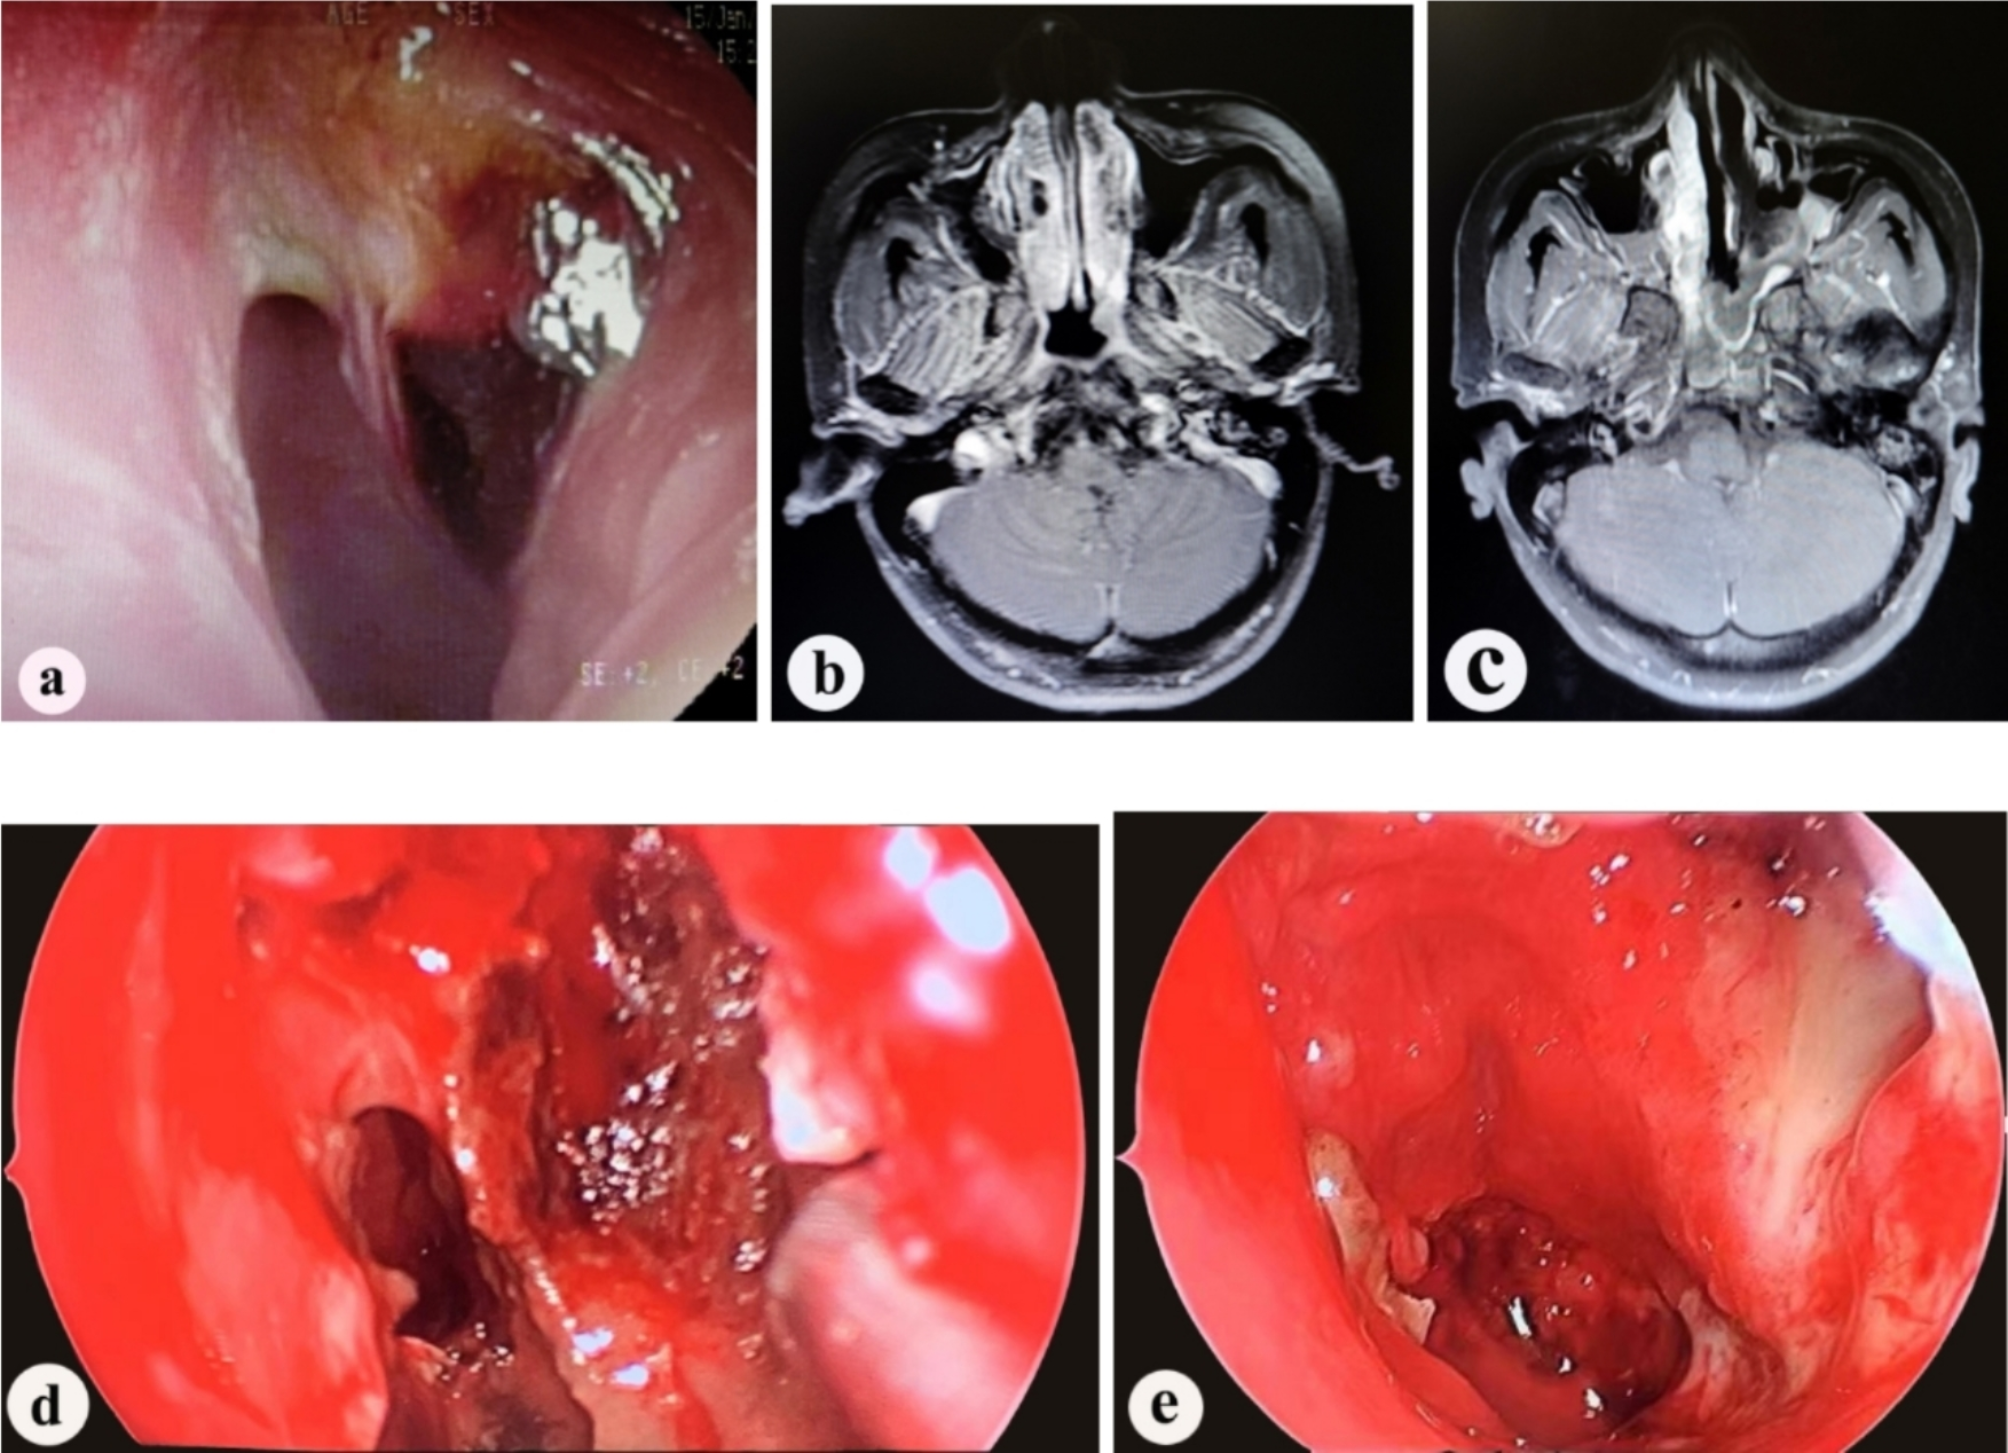

Fig. 1

(a) Preoperative nasopharyngeal endoscopy shows a mass in the left nasopharynx; ( b) Preoperative enhanced MRI shows enhancement of the mass in the left nasopharynx; (c) Enhanced MRI on the third day post-operation shows good blood supply to the nasal septal mucosal flap. Iodoform gauze packing is visible on the surface of the mucosal flap; ( d) On the fifth day post-operation, after removing the packing, nasal endoscopy shows good blood supply to the nasal septal mucosal flap; (e) One month post-operation, nasal endoscopy shows good blood supply to the nasal septal mucosal flap, which is closely attached to the nasopharynx.